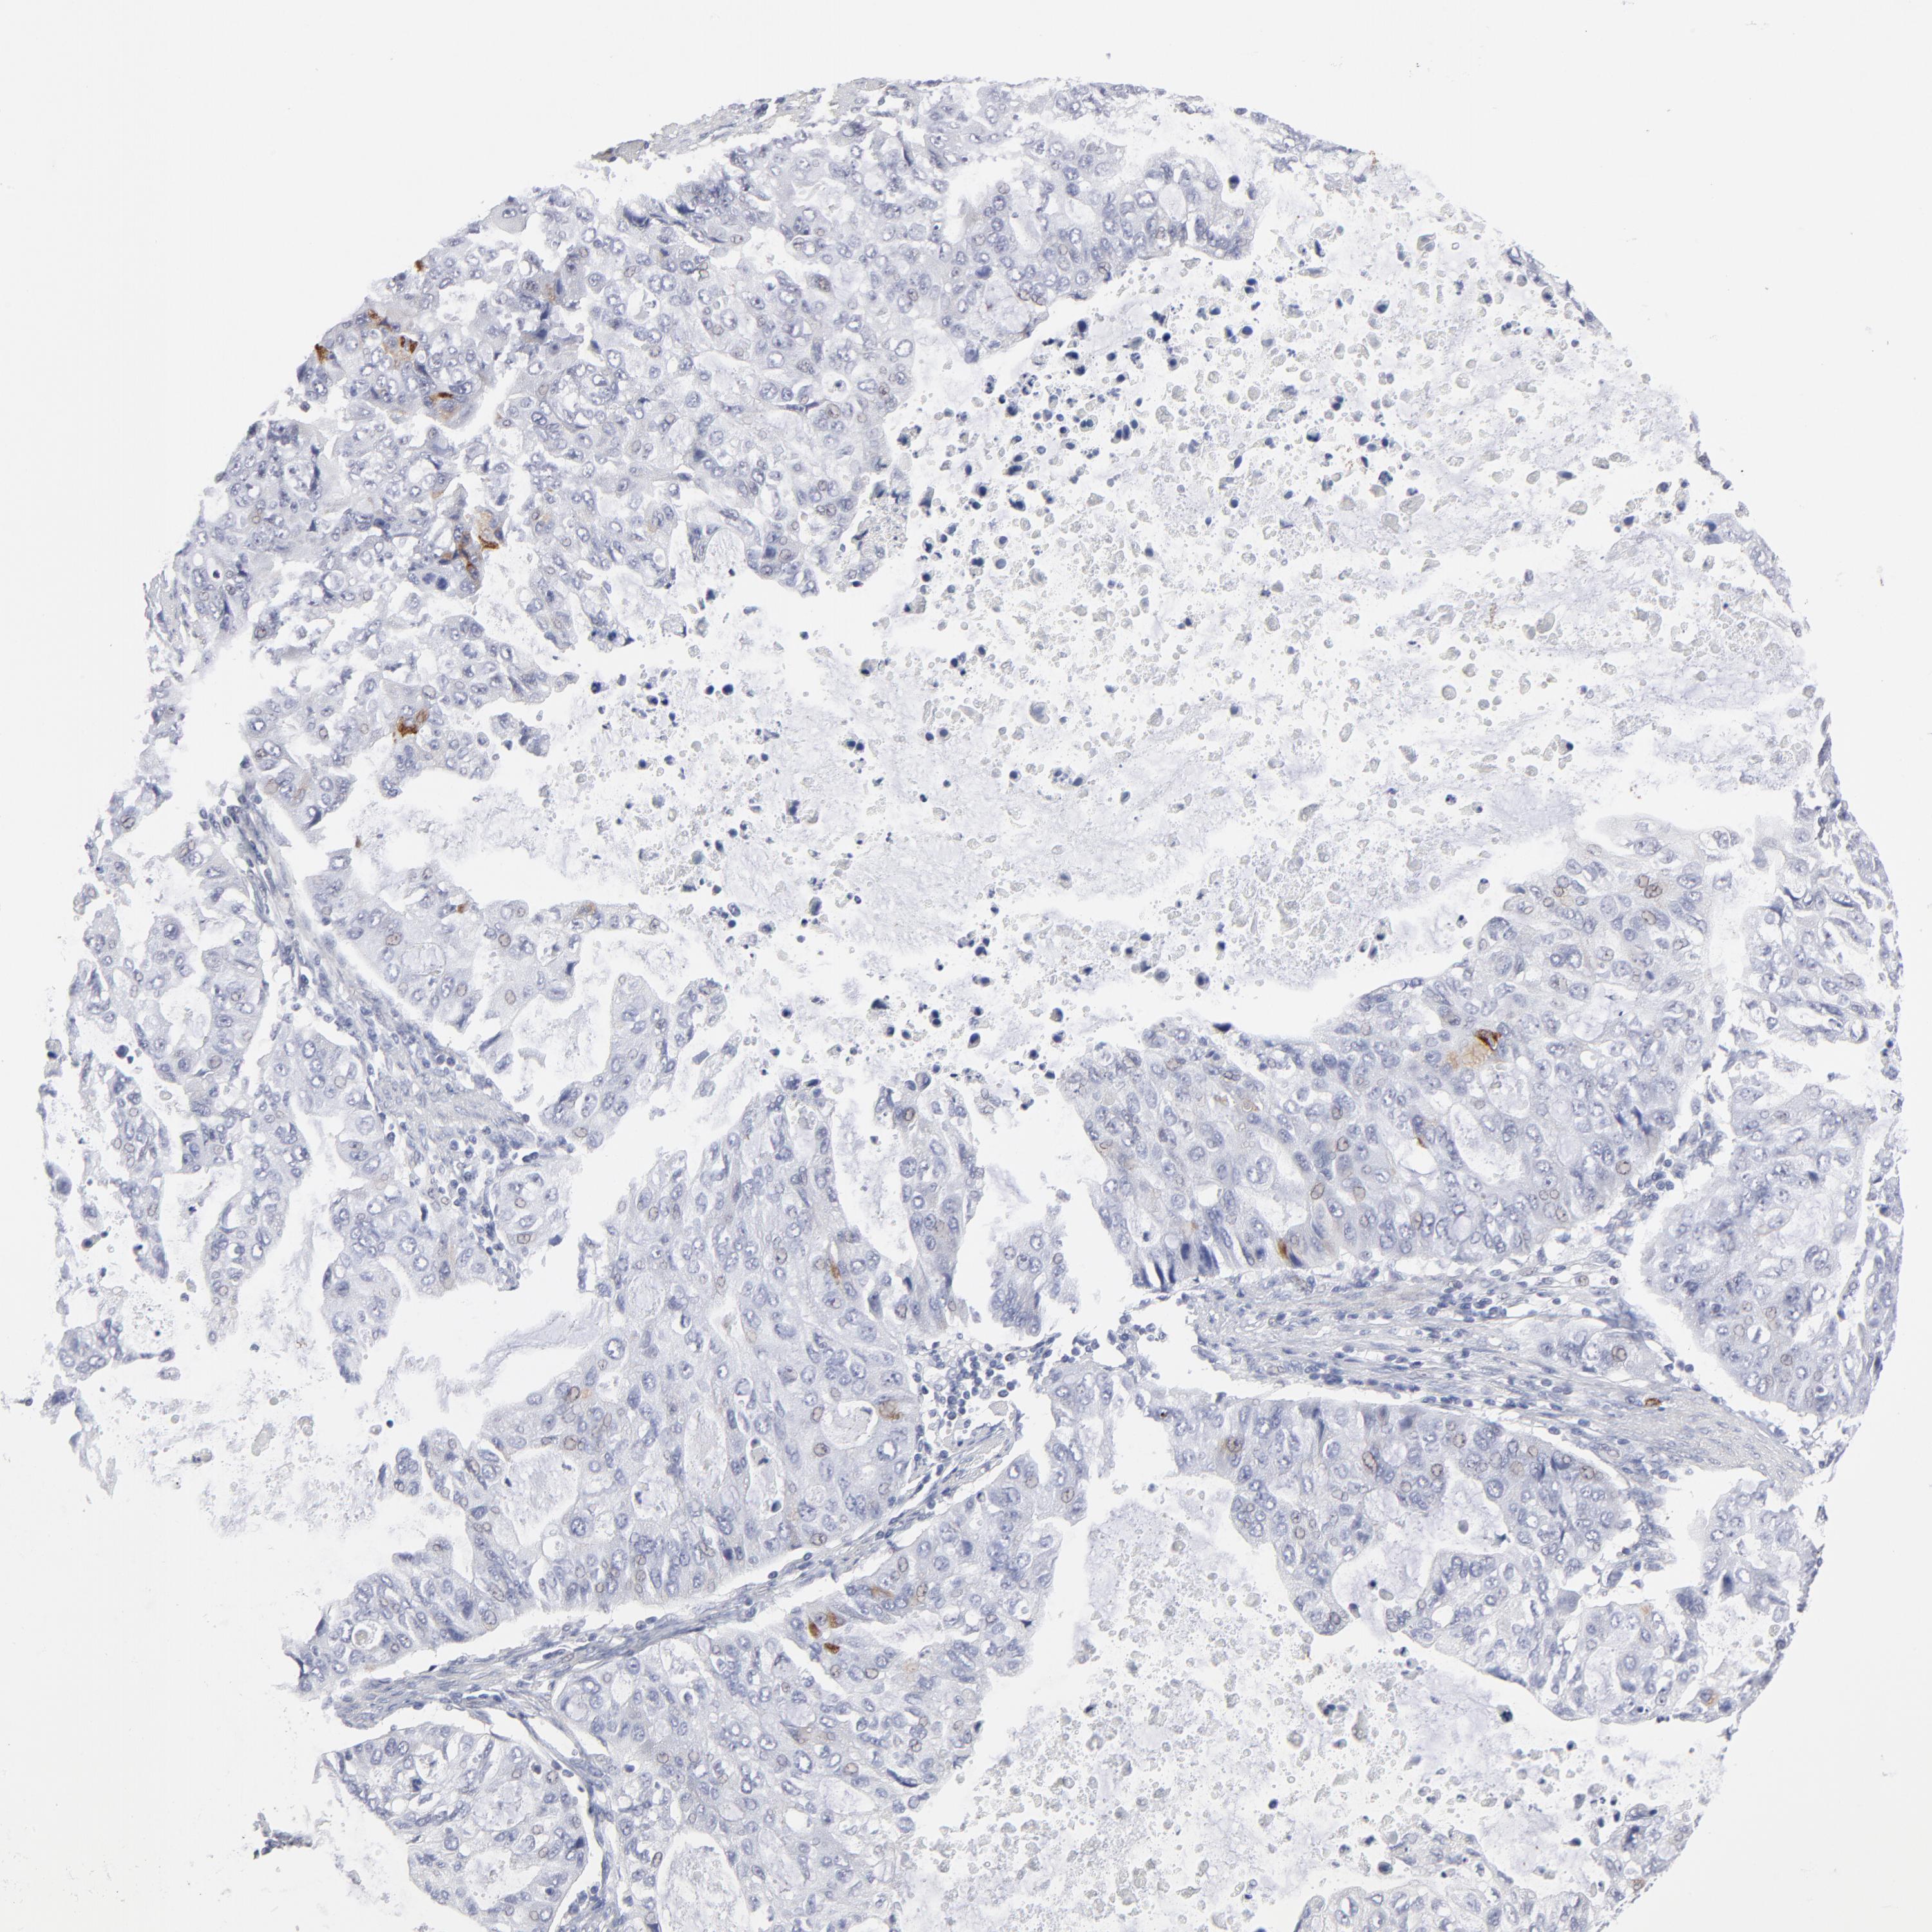

STOMACH CANCER - Protein expressioni

A mouse-over function shows sample information and annotation data. Click on an image to view it in a full screen mode. Samples can be filtered based on level of antibody staining by selecting one or several of the following categories: high, medium, low and not detected. The assay and annotation is described here.

Note that samples used for immunohistochemistry by the Human Protein Atlas do not correspond to samples in the TCGA dataset.

Antibody stainingi

Antibody staining in the annotated cell types in the current human tissue is reported as not detected, low, medium, or high, based on conventional immunohistochemistry profiling in selected tissues. This score is based on the combination of the staining intensity and fraction of stained cells.

Each image is clickable and will lead to virtual microscopy that enables deeper exploration of all samples and also displays staining intensity scores, fraction scores and subcellular localization as well as patient and tissue information for each sample.

Antibody HPA001429

Antibody CAB003836

Antibody CAB080233

Staining

High

Medium

Low

Not detected

Intensity

Strong

Moderate

Weak

Negative

Quantity

>75%

75%-25%

<25%

None

Location

Nuclear

Cytoplasmic/membranous

Cytoplasmic/membranous,nuclear

Adenocarcinoma, NOS

Adenocarcinoma, High grade